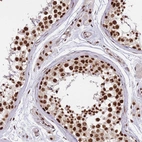

Immunohistochemical staining of human lymph node shows strong nuclear positivity in lymphoid cells.